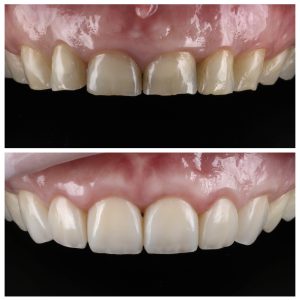

Visų nudilusių dantų plombavimas

Būklė, kai reikalingas visų nudilusių dantų plombavimas, susiformavo dėl dviejų priežasčių: amžiniai pokyčiai ir bruksizmas (dantų griežimas). Priekinių dantų atkūrimui buvo pritaikytas priekinių dantų estetinis plombavimas, plombuojant visą danties paviršių.

Estetinis plombavimas ant pacientės priekinių dantų

Galutinis rezultatas – natūrali ir autentiška šypsena. Tačiau svarbi ne tik atkurta dantų estetika. Mūsų odontologai pabrėžia, jog po gydymo, kai atliekamas visų dantų plombavimas ir atkūrimas, stipriai pagerėja sąkandžio būklė. Atkurta pilnavertė dantų anatomija apsaugo žandikaulio sąnarius nuo pertempimo ar priešlaikinio susidėvėjimo.

Visų dantų plombavimas prieš ir po Nudilusių dantų estetinis plombavimas prieš ir poVisų nudilusių dantų plombavimas prieš ir poViršutinis dantų lankas prieš ir po plombavimoApatinis dantų lankas prieš ir po plombavimo